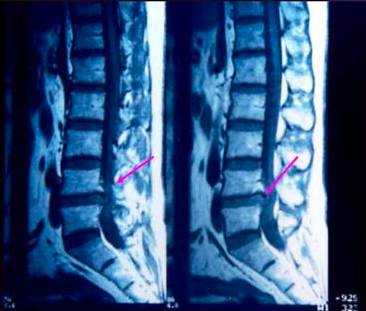

MRI:多节段间盘突出

MRI:间盘脱出

MRI:椎间盘退行性变,并向后突出

MRI:后外方突出压迫神经根

脊髓造影、CT、MRI、椎间盘造影等方法,能准确地作出病变间隙、突出方向、突出物大小、神经受压情况及主要引起症状部位的诊断,但不能仅依据CT、MRI而诊断。